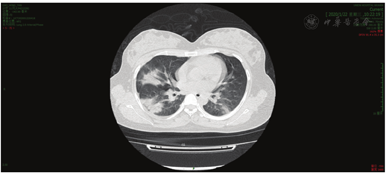

A full blood count found a haemoglobin concentration of 111 g/dL and a leucocytosis count (3.66 × 109/L, normal range: (3.5-9.5) × 109/L), lymphocyte was (1.05 × 109/L) which was decreased according to the normal range of (1.1-3.2) × 109/L. The level of C-reactive protein (CRP) was a little higher than normal 10.63 mg/L. Coagulation profile, and serum biochemical test including renal and liver function, and creatine were normal. A CT of the patient’s lung showed bilateral multiple lobular and subsegmental areas of consolidation and bilateral ground-glass opacities (Fig. 1). B-ultrasound examination of the fetus showed that the depth of amniotic fluid was 2.0 cm which indicated oligohydramnios and cervical length was 3.7 cm.